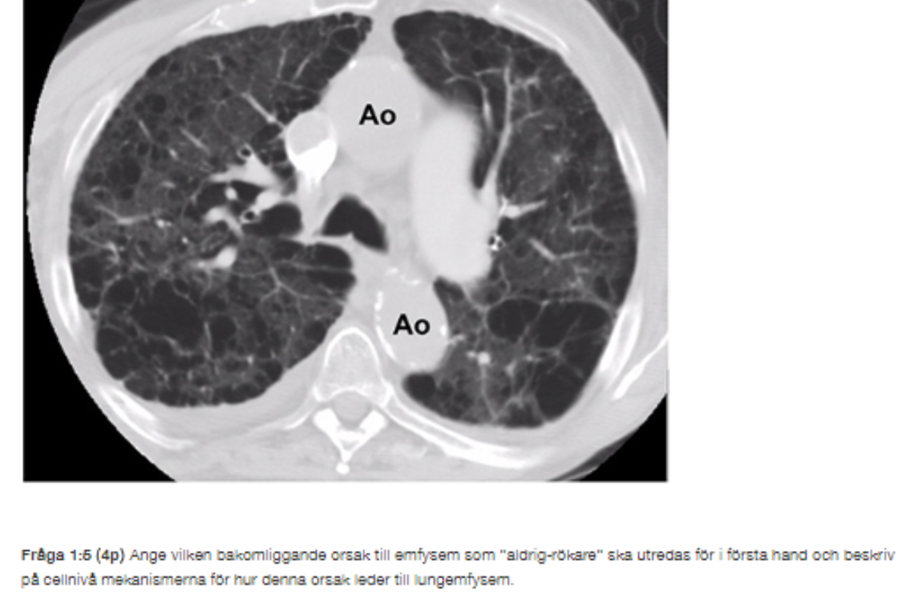

När en tidigare komprimerad lunga, som är tom på luft, snabbt expanderas kommer tidigare komprimerad kärlbädd i lungan att öppna upp sig. När blodcirkulationen så plötsligt återställs finnsd et risk för vätskeutträde från kapillärer in i lungans vävnader och ut i lungans alveoler. Ett så kallat re-expansionslungödem kan uppträda i höger lunga. Tillståndet är mycket allvarligt. En akut datortomografi (DT) av thorax visar dock inga sådana tecken. Den relativa hypoxemin förklaras istället av ett emfysem (se bild). Eftersom Jonathan är ”aldrigrökare” blir du överraskad att han har ett så avancerat emfysem med så stora blåsor. Med tanke på Jonathans unga ålder blir du också överraskad att hans aorta(Ao)vägg redan är så pass förkalkad (se bild)

Brist på enzymet alfa-1-antitrypsin. En patogen mutation i alfa-1-antitrypsin (α1-AT) leder till sekretion av reducerade mängder av proteinet från hepatocyter till cirkulationen och i lungvävnaden lokalt producerat α1-AT från typ II pneumocyter. Förlusten av ett adekvat skydd mot elastasaktivitet leder till emfysemutveckling. Intracellulär ansamling av polymeriserat α1-AT i det endoplasmatiska retiklet (ER) i typ II pneumocyter kommer att skada cellen och omgivande lungvävnad. Detta kan resultera i sekretion av kemokiner, nuclear factor (NF)-κB signalering och därmed ökad känslighet för apoptos. Det sker en rekrytering av neutrofiler och dessa cellers förmåga att döda bakterier hämmas av den effekt ett överskott av elastas har på ”interleukin (IL)-8/CXCR1 pathway”. Alfa-1-AT, med ursprung från en kombination av lokal syntes och passiv diffusion från cirkulationen, kommer att leda till en extracellulär polymerisering i interstitiet. Sådana interstitiella polymerer kommer att lokalt motverka kemotaktiska stimuli från alveolerna, vilket leder till en förlängning av neutrofilernas passagetid genom interstitiet och sekundärt till detta till en interstitiell ansamling av neutrofiler. I interstitiet kommer polymererna att aktivera neutrofilerna och stimulera dessa till degranulering. Därmed blir fokus för proteolys i mitten av den extra-cellulära vävnaden och åtföljande vävnadsdestruktionen blir hellre panacinär än centriacinär.